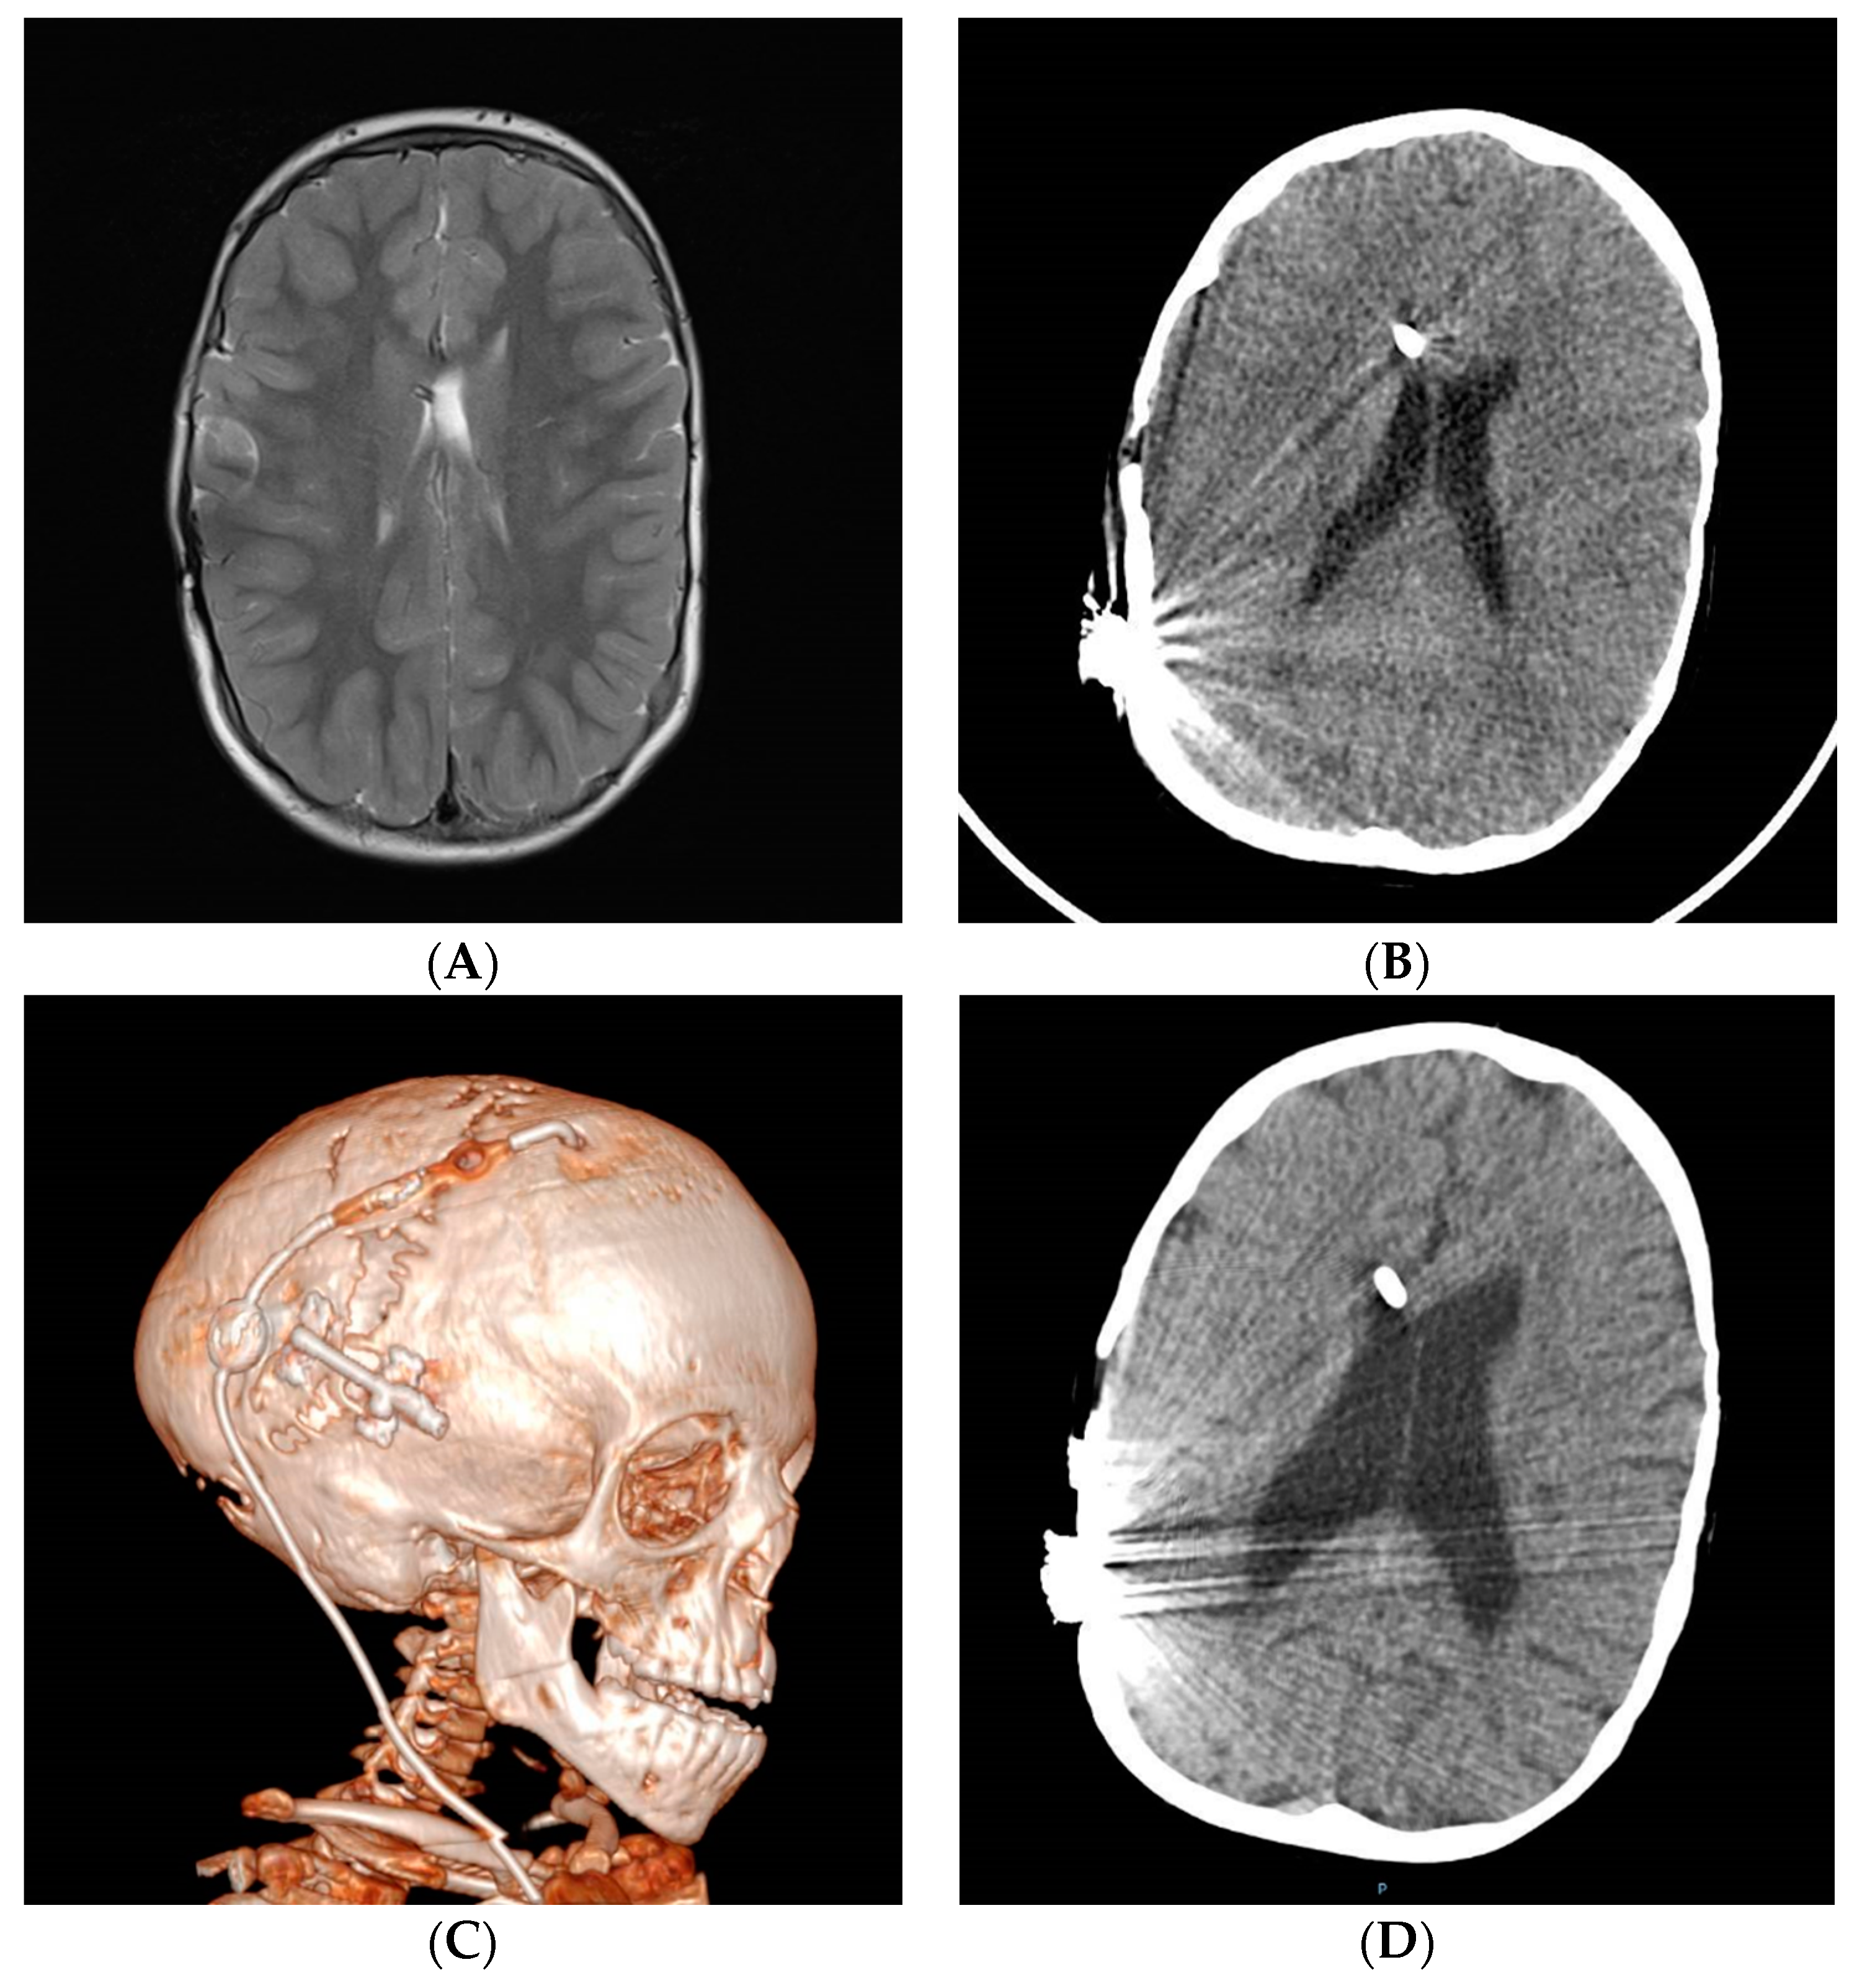

Despite the superb contributions made by many authors on the topic of shunt overdrainage in the last half century, severe forms of shunt overdrainage syndrome still exist and an active prevention policy is lacking in many centers. Universally agreed-upon diagnostic criteria and classifications are necessary, probably based on a better understanding of the pathophysiological mechanisms and relationships among them. In this work we have proposed an integrative model of pathophysiology with clinical manifestations, radiological findings and ICP patterns to help determine the best (sometimes stepped) management strategy. Differences between pediatric patients and adults are based on the different etiologies, the characteristic CCD that occurs in infants and the duration of the overdrainage period and its influence on the complexity and severity of stablished pathophysiological mechanisms. Figure 4 offers an algorithm for management based on pathophysiology and Figure 5 illustrates the idea. The model is summarized in Table 1. Shunt optimization by prevention or correction of siphoning with GV or ASD is mandatory as the first therapeutic measure to avoid or minimize CSF isolation, CCD and venous hypertension, making shunt overdrainage less severe and easier to manage. Shunt optimization or transferal and neuroendoscopy may be recommended when ventricular collapse and cerebrospinal fluid isolation appear. Cranial expansion may be useful in congenital or acquired craniocerebral disproportion and shunting the subarachnoid space in communicating venous hydrocephalus and idiopathic intracranial hypertension.

Figure 5.

An 8-year-old patient with syndromic craniosynostosis and hydrocephalus, shunted at birth (also see Figure 3). Posterior cranial vault expansion by distraction osteogenesis performed before 1 year of age. The patient harbored an adjustable valve with FCD and in-line fixed antigravitational device. Episodes of headache and stiffness appeared, with slow valve refilling after pumping. (A) Ventricular collapse on MRI. (B) Improvement in ventricular size after shunt optimization (upgraded GV implanted in line) but symptoms only partially improved. (C) Re-do posterior cranial vault gradual distraction was performed with clinical and (D) significant radiological improvement.